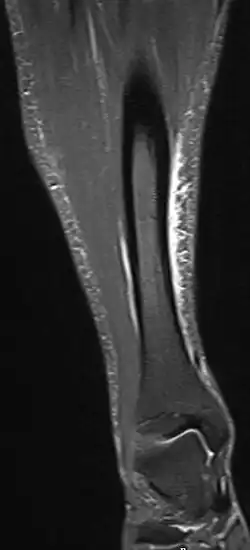

An der stark belasteten Stelle am Schienbein treten häufig Knochenhautentzündungen auf. Ein Schmerz nach dem Sport kann ein erstes Anzeichen einer Knochenhautentzündung sein. In allen Fällen sollte unverzüglich ein Arzt aufgesucht werden. Die Diagnose kann mit einer MRT (Kernspintomographie) gestellt werden (die entzündete Knochenhaut gibt in fettunterdrückten Aufnahmen ein charakteristisches helles Signal); insbesondere zur Unterscheidung zur Stressfraktur ist die MR geeignet.[4]